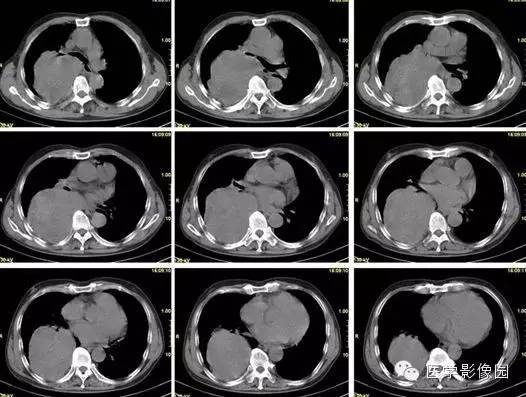

【病例】巨大中央型肺癌1例